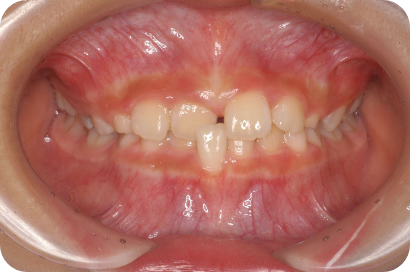

Sさん

Before

After

- 形態:

- 機能:

- 期間や回数:

- 治療費:

- メリット:

- リスクと副作用: